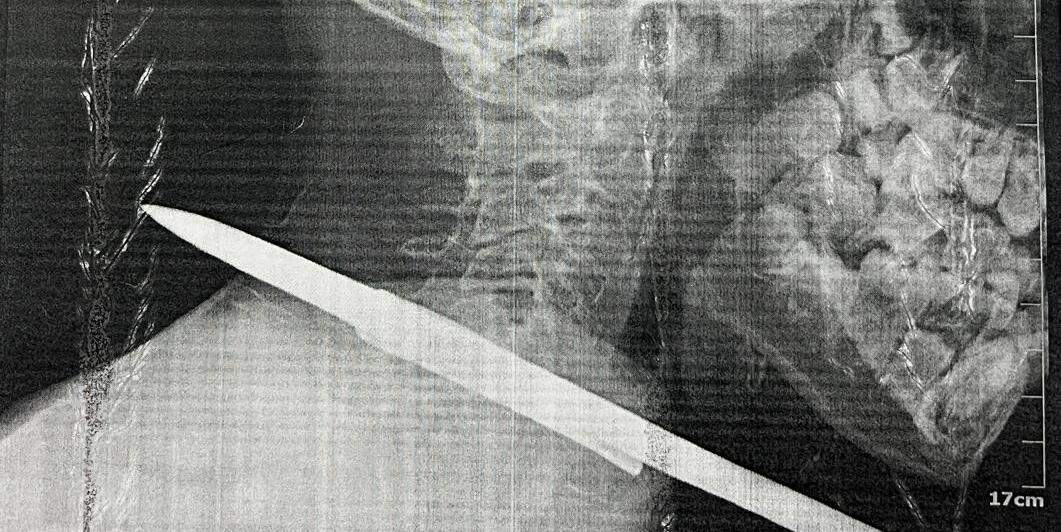

Menino sobreviveu a acidente com arpão de pesca no pescoço em Santarém, no oeste do Pará. (Divulgação / Prefeitura Municipal de Santarém)

Um arpão de pescador foi retirado do pescoço de uma criança de 11 anos após cirurgia no Hospital Municipal de Santarém Dr. Alberto Tolentino Sotelo, na última segunda-feira (07/10), no município de Santarém, na região oeste do Pará. O menino chegou no hospital depois de um acidente grave durante uma pescaria e passou por uma cirurgia de emergência para a retirada do objeto.

“No pescoço passam várias estruturas que são muito nobres para o nosso organismo. Passa ali a artéria carótida, a veia jugular, e o arpão estava atravessado a centímetros dessas duas estruturas. Então, por pouco, não foi um acidente muito grave. Foi um milagre”, relatou o médico cirurgião Augusto Aguiar, que fez a retirada de uma vara de arpão que estava atravessada no pescoço do paciente.